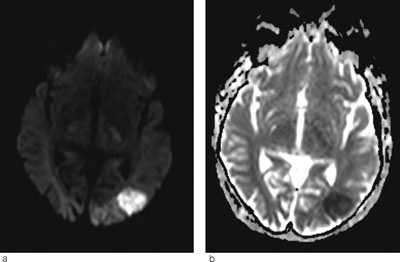

Hjerneødem kan være cytotoksisk (cellulært) eller vasogent (interstitielt). Ofte foreligger det en kombinasjon. Ved hjerneinfarkt dominerer det cytotoksiske ødemet og celledød (fig 3a-b). Ved posterior reversibel encefalopati-syndrom får man et vasogent ødem som i utgangspunktet er reversibelt, men som uten behandling kan utvikles til cytotoksisk ødem og gi permanent cellulær skade. Ved hjelp av MR med diffusjonsvekting (DWI) og ADC-kart kan man skille mellom cytotoksisk og vasogent ødem. Ved MR med diffusjonsvekting er det høyt signal ved cytotoksisk ødem, mens det vanligvis er lavt signal eller ingen signalendringer ved vasogent ødem. I noen tilfeller får man likevel høyt signal ved posterior reversibel encefalopati-syndrom. Dette skyldes at DWI-resultatet er satt sammen av bidrag fra både T2-vekting og diffusjonsvekting. Høyt signal på T2 kan derfor skinne igjennom til diffusjonsbildet. Dette var også tilfellet hos vår pasient (fig 1c). Det er derfor viktig med ADC-kart, hvor bidraget fra T2 er fjernet og man får et rent diffusjonsbilde (7). ADC-kart viser alltid lavt signal ved cytotoksisk ødem og høyt signal ved vasogent ødem, som ved posterior reversibel encefalopati-syndrom (fig 1d).